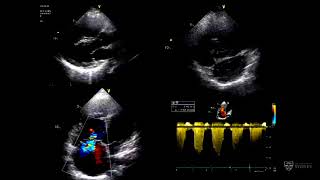

This presentation by Prof Greg Scalia explores interventional devices for managing adult congenital…